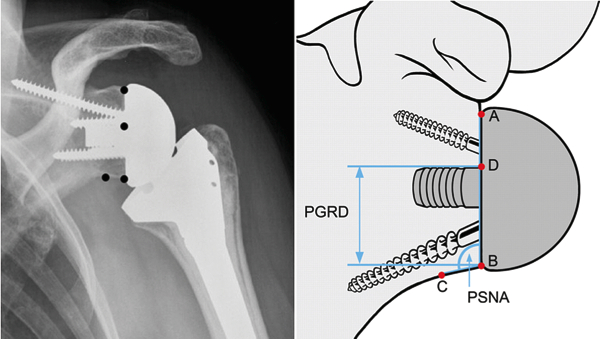

The reverse shoulder arthroplasty is a solution that directly addresses chronic deficiencies of a torn rotator cuff, compensating for its weakness or absence by rearranging the anatomy.

“In this procedure, the ball portion of the joint is taken from the humerus side and moved to the shoulder blade or scapula side and attached with an implant or prosthesis. The socket is moved to the upper end of the humerus side,” says Dr. Sabesan. “No other joint replacement surgery changes the normal anatomical structure like this.”

Like traditional shoulder replacement surgeries, the arthritic joint surfaces are replaced with a highly polished metal ball attached to a plastic socket, but in the reverse procedure, the socket and metal ball are switched. The reverse procedure constrains the ball in a cup that is inserted into the end of the humerus, and the metal ball is attached to the shoulder bone. The reversal increases tension of the deltoid muscle, producing more torque. In this way, the deltoid muscle compensates for the loss of rotator cuff by becoming the primary elevator of the shoulder joint and making it easier for a patient to raise his or her arm. Yet, range of motion remains limited.